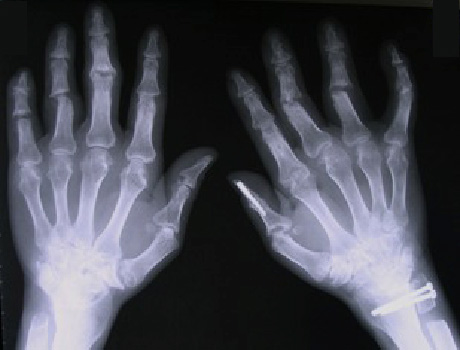

変形した両手指や手関節を手術しました